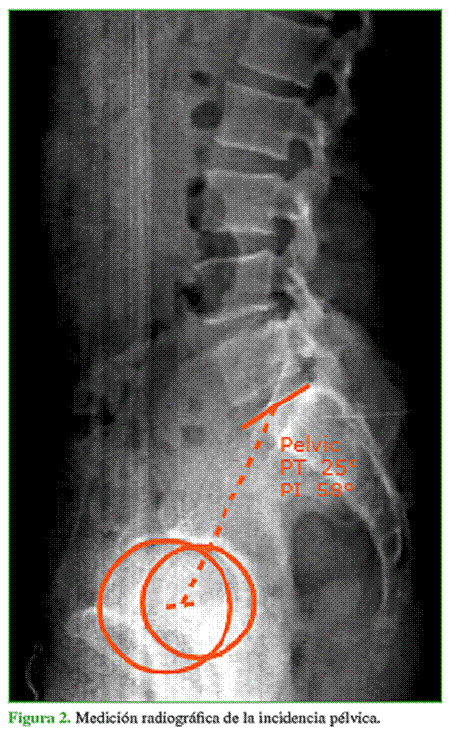

La incidencia pélvica (IP), ángulo descrito por Duval-Beaupère, determina la posición del platillo superior de S1 y su relación con el centro de rotación de ambas caderas.4 Única e individual, otorga información sobre la anatomía sagital de la pelvis. Es variable con el crecimiento y estable en la madurez esquelética. La invariabilidad de este ángulo en el adulto está sujeta a la estabilidad de la unión sacroilíaca.4,5 La IP promedio es 55° ± 10° con un amplio rango normal (de 35° a 85°).6

-    IP (ángulo entre el centro de rotación de ambas caderas y la perpendicular al centro del platillo superior del sacro) (Figura 2).5